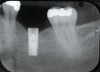

Fig 8. Loss of restoration and subsequent tissue overgrowth from broken abutment screw as shown in the radiograph (Fig 9).

Figure 8

Fig 9. Radiograph depicting fractured screw inside of the implant.

Figure 9

Fractured screws are challenging to retrieve, particularly when they are abutment screws. If the screw head is accessible, a hemostat can be used to remove it. However, when the screw breaks inside the implant (Figure 8 and Figure 9), removal can be highly complicated in order not to damage the implant’s internal threads. Therefore, many implant manufacturers have developed screw-retrieval kits. Because it is critical to be able to visualize the area, magnification using loupes and a surgical microscope may be necessary.8 Additional methods can be used to remove the fractured screw. A ¼ round bur set on a high speed can be used by lightly activating it, touching only the side of the screw. After repeating this technique several times, the screw may be able to be backed out with an explorer tip. Ultrasonic tips with copious irrigation may also dislodge the screw.7,20 In cases in which this fails, a small slot can be made in the head of the screw to back it out.21 If screw threads have been damaged during retrieval, they may be retapped using a tool obtained only from the implant manufacturer.7